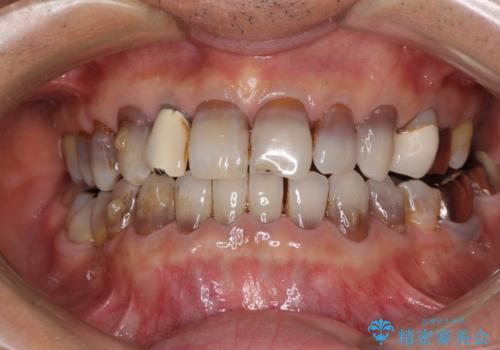

インビザラインは四六時中上下のマウスピースを介した咬合状態となるため、治療過程にて奥歯が接触しないという状態が続くことがあります。

奥歯の非接触は機能面において大きな障害であるため、この問題を解決しない限り矯正治療を終えることはできません。

インビザラインでの矯正治療が長期化してしまう要因の1つです。